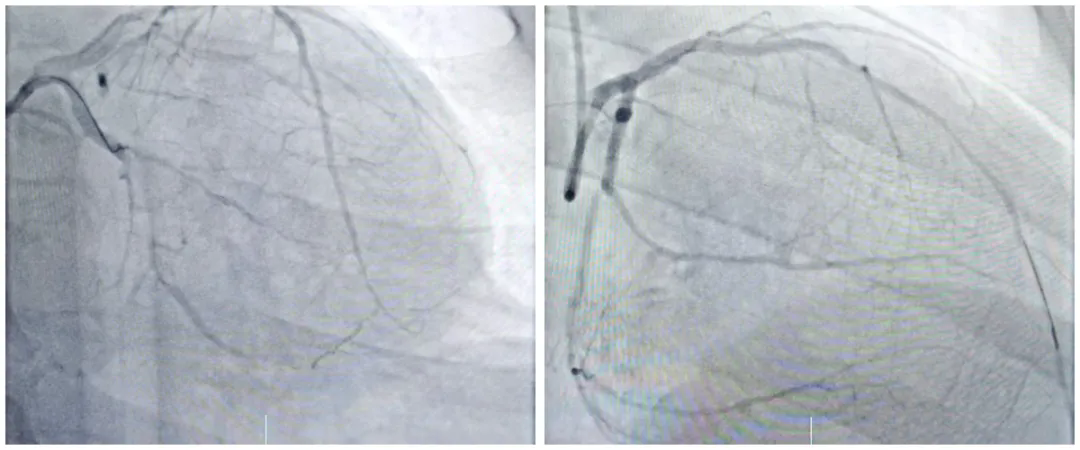

近日,我院心血管内一科团队成功为一名辗转多家三甲医院、濒临换心的37岁重症心脏病患者实施 IABP(主动脉内球囊反搏)支持下双支闭塞病变开通术,这场历时43分钟的精准手术,为患者重燃生命希望,展现了我院在重症心...